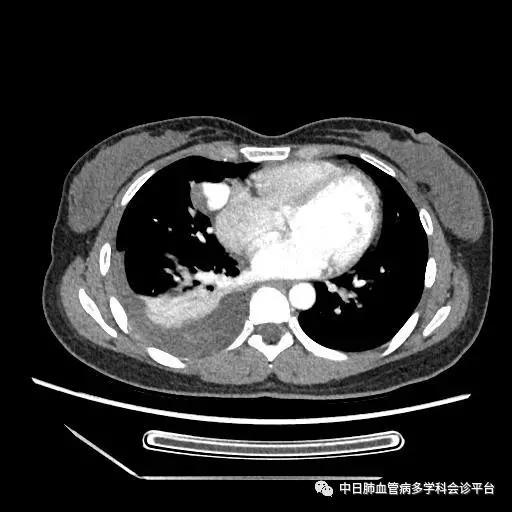

胸部CT(2016-10-24)

(5). 超声示心脏结构和功能正常,胸部CT示右侧大量胸腔积液,右肺部阴影。

此病例诊断的转折点是超声心动图及右心声学造影示肺血管水平右向左大量分流。回过头来我们再仔细阅读胸部CT平扫时,所见的肺部阴影为瘤样扩张的肺血管,并非恶性占位性病变,CTPA没有见到明显的肺栓塞征象,因此可以除外肺栓塞诊断。患者大量深红色血性胸腔积液,结合突发胸痛、晕厥的临床表现,入院后第2天血常规示血色素降至81g/L,考虑为急性胸腔出血,至于胸腔内出血的原因,成为下一个锁定的目标。

胸部增强CT:右肺中叶动静畸形并瘤内附壁血栓形成,右侧胸腔积液,右下肺膨胀不全。